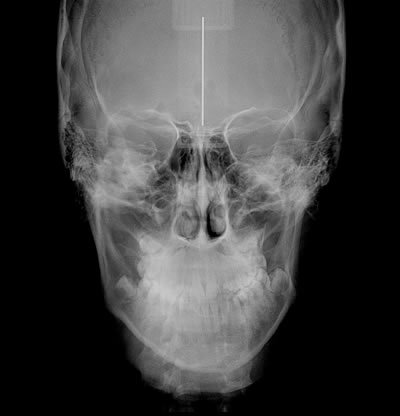

Póstero-Anterior (PA) Frontal ou Telerradiografia Frontal